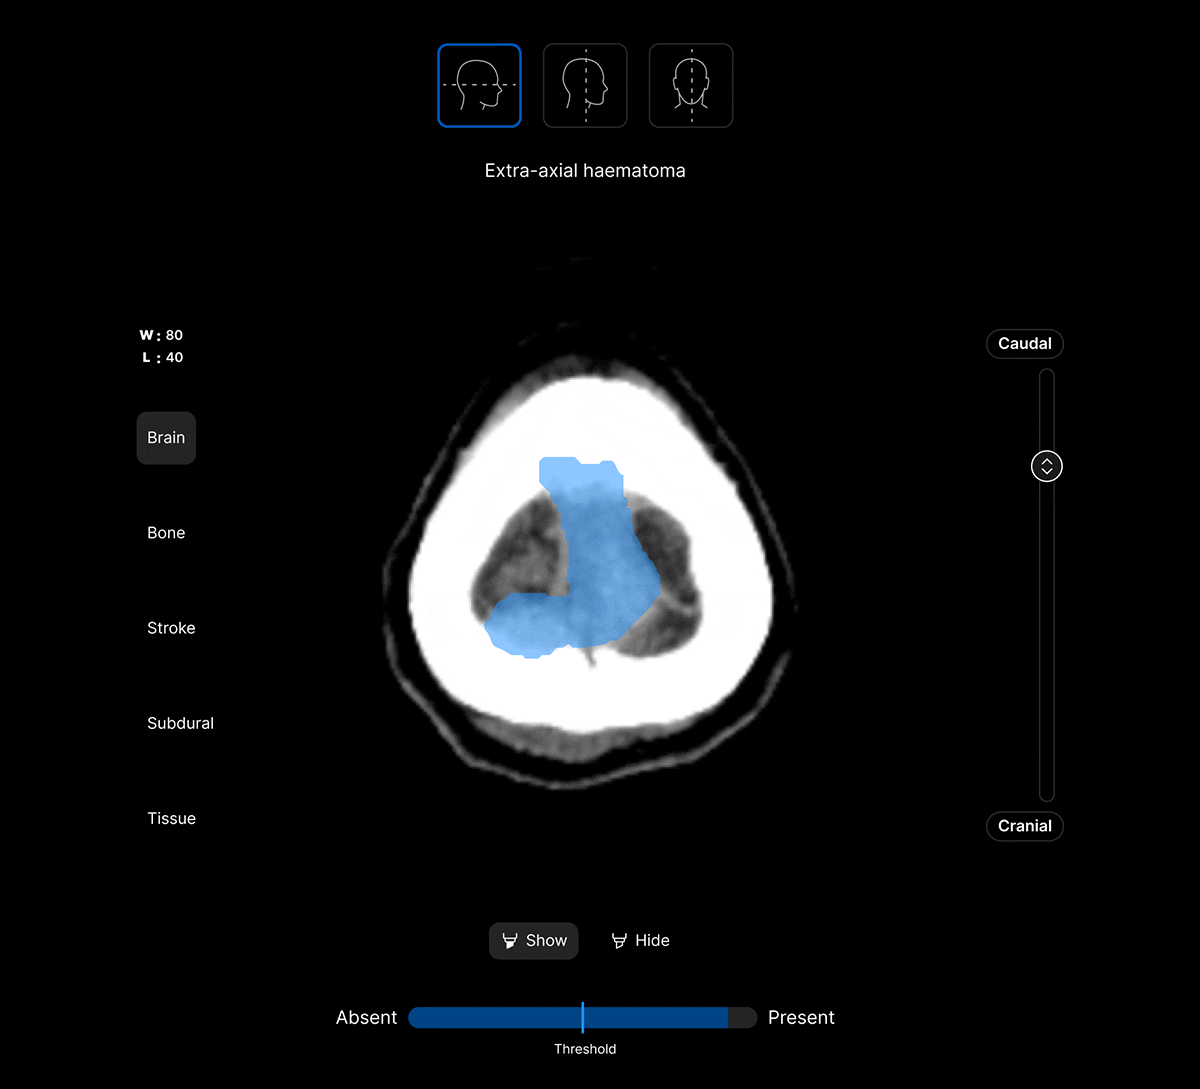

Coloured overlays on the image to quickly locate findings.

Explainable AI feature to improve AI interpretability and improve clinical decision-making.

View findings within preset subdural, bone, brain, soft tissue and stroke views to provide additional context to the AI results.

Customisable thresholds, for individual findings (to optimise for sensitivity / specificity) to tailor the workflow to your clinical setting or population.